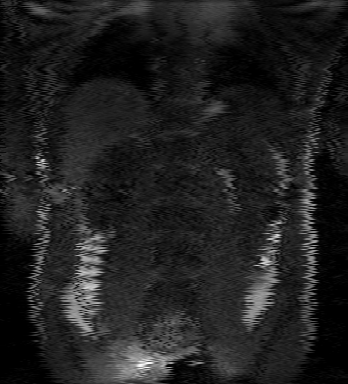

Tables 1 and 2 show our quantitative results: PSNR between the style (image we want to transfer style from) and generated image, SSIM and MS-SSIM between the content (image we want to take structure from) and generated image and finally, our proposed weighted SSIMs. For each style transfer direction and metric, our method consistently outperforms the other approaches. Figures 2 and 3 qualitatively highlight the good results of our method on 2D and 3D datasets. In addition, quantitative results on both figures show that our proposed metric preserves qualitative ordering of results for both style and content. In comparison, metrics such as SSIM struggle to accurately correlate to visual results.

(C) CW-SSIM: 0.68

(S) CW-SSIM: 0.61

(C) CW-SSIM: 0.54

(S) CW-SSIM: 0.51

(C) CW-SSIM: 0.42

(S) CW-SSIM: 0.67

(C) CW-SSIM: 0.93

(S) CW-SSIM: 0.73